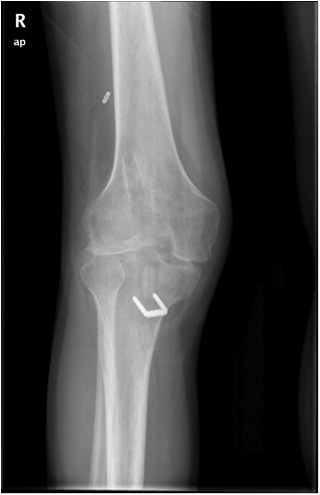

Fracture

Patella fracture

Tibial fracture

If using back up fixation such as a fracture, ensure sufficient distance from tibial tunnel

Alternatively, use a screw-post fixation